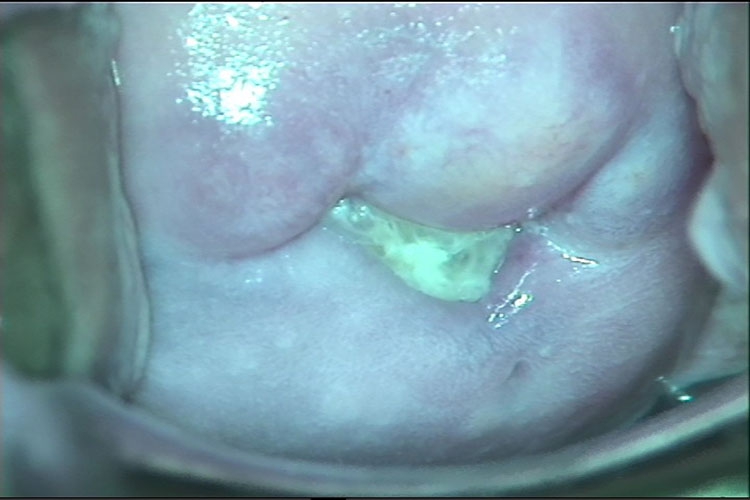

凝乳块状或豆渣样白带为外阴阴道假丝酵母菌病的特征,常伴严重外阴瘙痒或灼痛。